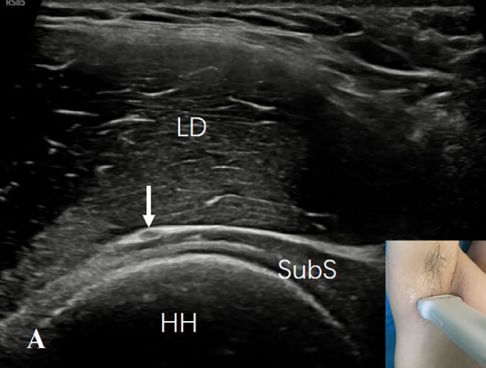

2)肩胛下肌的前方:患者平躺,肩部完全外展以暴露整个腋窝。探头水平放置在肱骨头上。观察到肩胛下肌位于肱骨头的上方,腋神经(AN)的短轴位于肩胛下肌和背阔肌之间,呈点状低回声(图3A)。旋转探头,显示腋神经在肩胛下肌表面的长轴切面,呈带样低回声(图3B)。

图3A:探头水平放置在肱骨头(HH)上。可见肩胛下肌(SubS)位于肱骨头上方。腋神经(AN)的短轴(箭头)在肩胛下肌(SubS)和背阔肌(LD)之间呈点状低回声。

图3B:旋转探头显示腋神经(AN)的长轴(白色箭),在肩胛下肌(SubS)表面呈低回声带。A,腋动脉;V,腋静脉